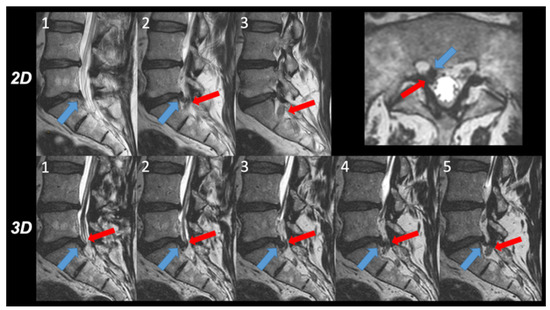

- 2D T2w TSE sequence: acquisition sagittal, repetition time (TR) 3000 ms, echo time (TE) 100 ms, flip angle 90°, echo train length 20, number of echoes 1, FOV 160 × 270 × 65 mm, slice thickness 4 mm, acquired voxel size 0.75 × 0.95 × 4.0 mm3, reconstructed voxel size: 0.63 × 0.63 × 4.0 mm3, number of signal averages (NSA) 2.0. Acquisition time 03 min 02 s.

- 3D T2w TSE sequence: acquisition sagittal, DRIVE pulse yes, TR 1300 ms, TE 95 ms, flip angle 90°, echo train length 50, number of echoes 1, field of view (FOV) 200 × 300 × 90 mm3, acquired voxel size 0.8 × 0.8 × 1.0 mm3, reconstructed voxel size 0.4 × 0.4 × 0.5 mm3, number of slices 180, acceleration: Compressed SENSE factor 7.0, NSA 1.0, acquisition time 04 min 46 s. This sequence was accelerated with the compressed SENSE acceleration technique that uses a variable density Poisson disk-sampling scheme followed by iterative reconstruction. A more detailed description of this acceleration technique can be found elsewhere [10,13]. The sequence was generally acquired in the sagittal plane of the section parallel to the spinal column. In patients with scoliosis, however, a secondary curved sagittal reconstruction parallel to the scoliotic lumbar vertebrae was obtained. Curved transverse reconstructions were computed parallel to the individual disc levels.